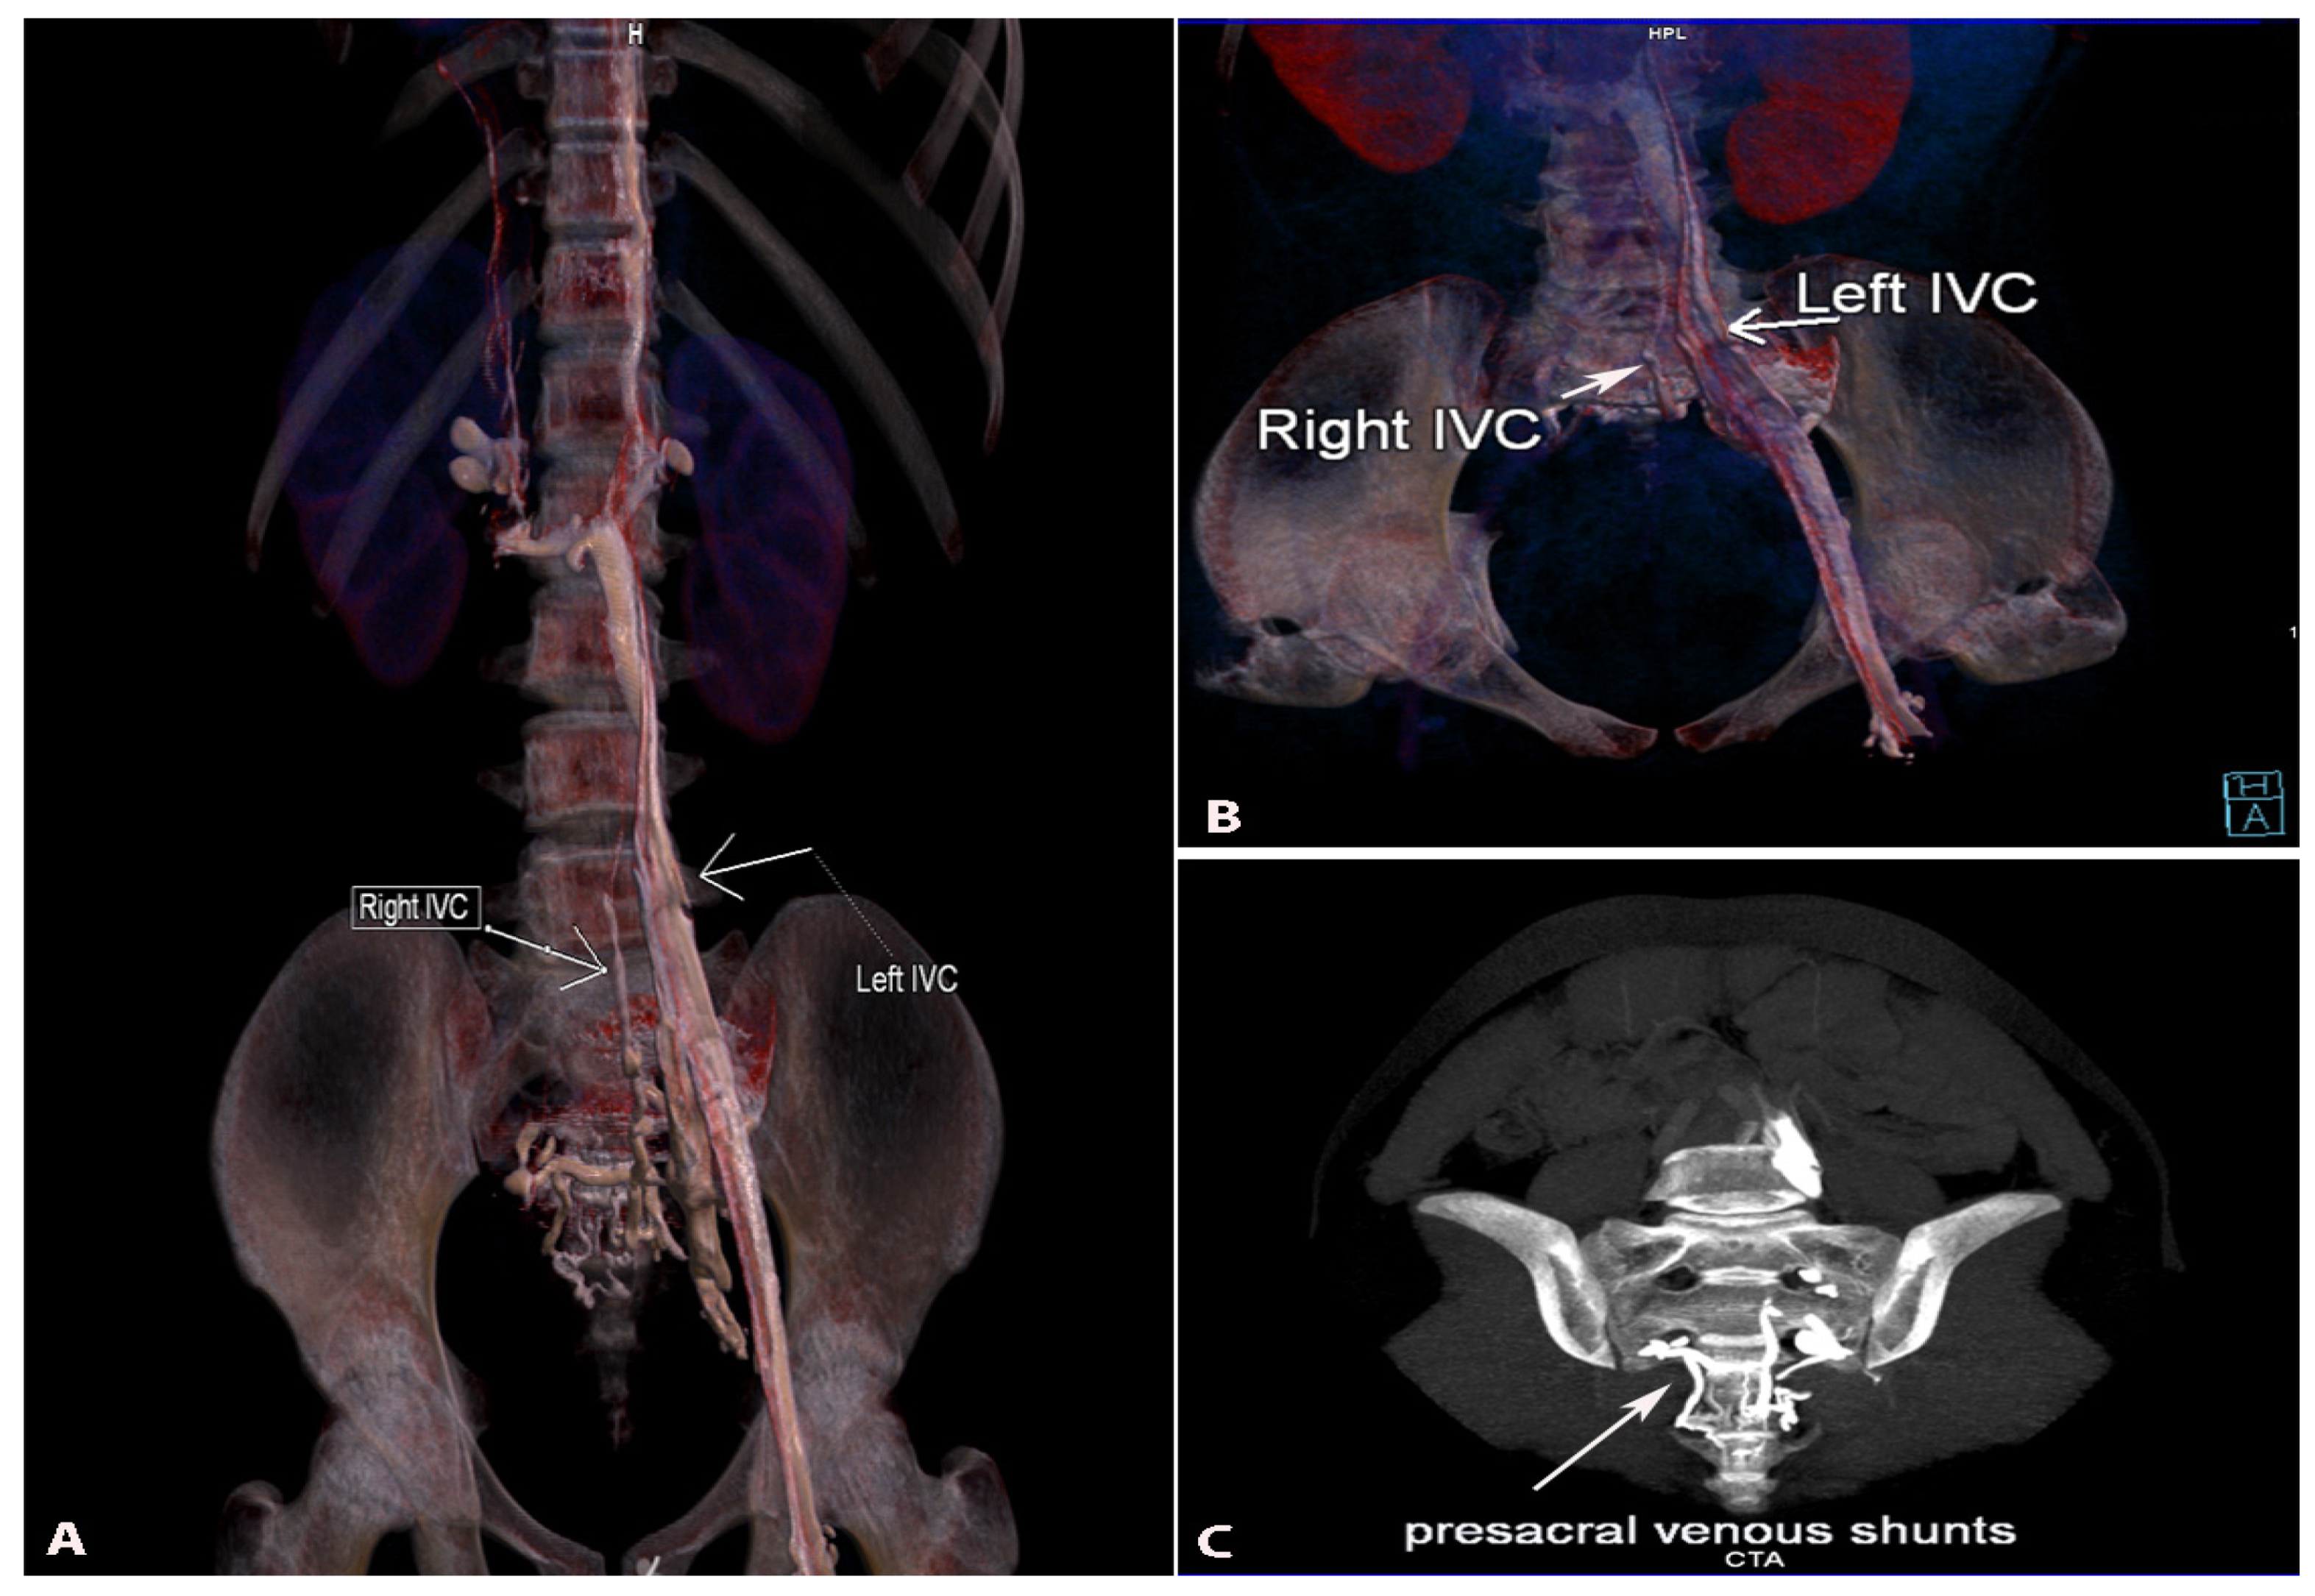

9.4.2. Duplication of the Inferior Vena Cava

Surgical Considerations

9.4.3. Marsupial Inferior Vena Cava